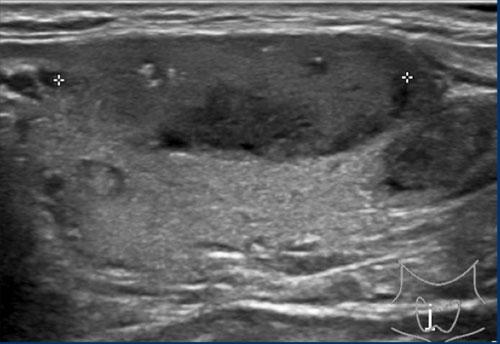

Trường hợp 3

Quan sát hình ảnh và xác định điểm TI-RADS.

Cuộn hình ảnh để xem điểm TI-RADS.

Lưu ý các tiêu điểm tăng âm nhỏ hiện diện.

Tổng cộng 6 điểm tương ứng với điểm TI-RADS là 4.